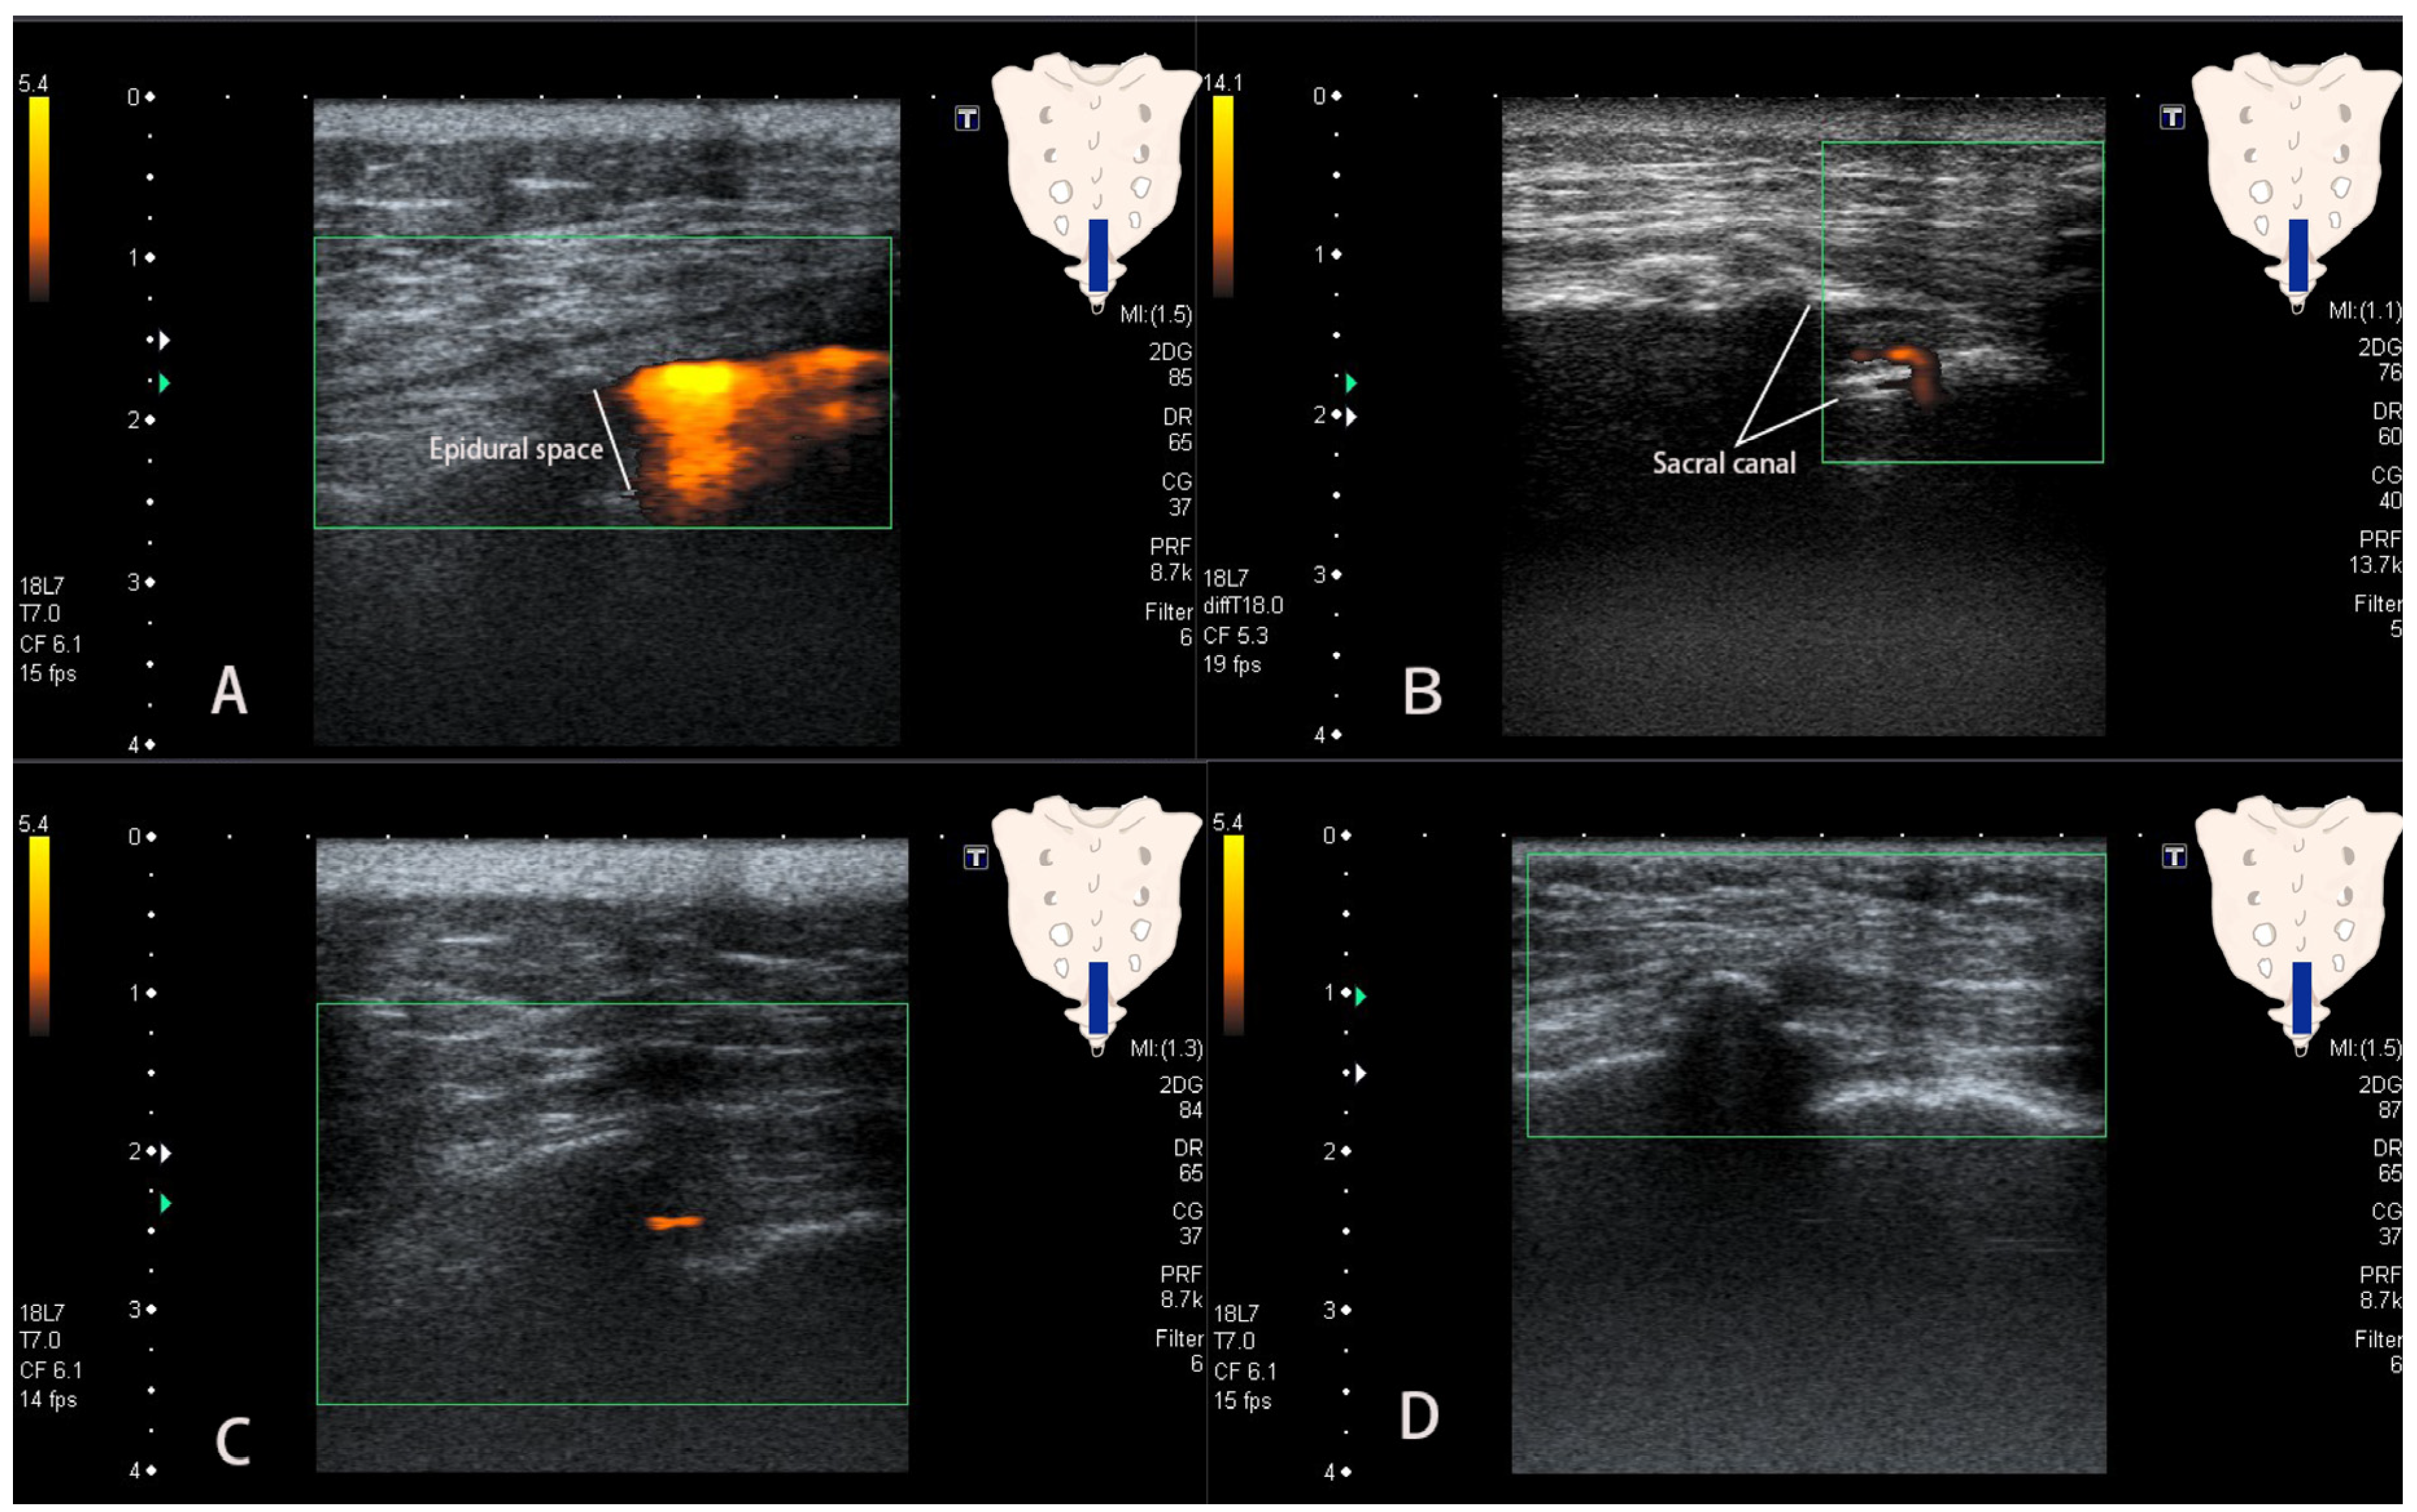

| Flow pattern | <0.001 | ||

| Patch sign | 2 | 237 | |

| Earthworm sign | 7 | 0 | |

| Tubular sign | 0 | 25 | |

| Absent flow | 1 | 5 |

| Patch sign | 88.8 [84.35–92.29] | 80.0 [44.39–97.48] | 4.44 [1.28–15.34] | 0.14 [1.28–15.34] |

| Earthworm sign | 70 [34.75–93.33] | 100 [98.63–100] | ∞ | 0.3 [0.12–0.77] |